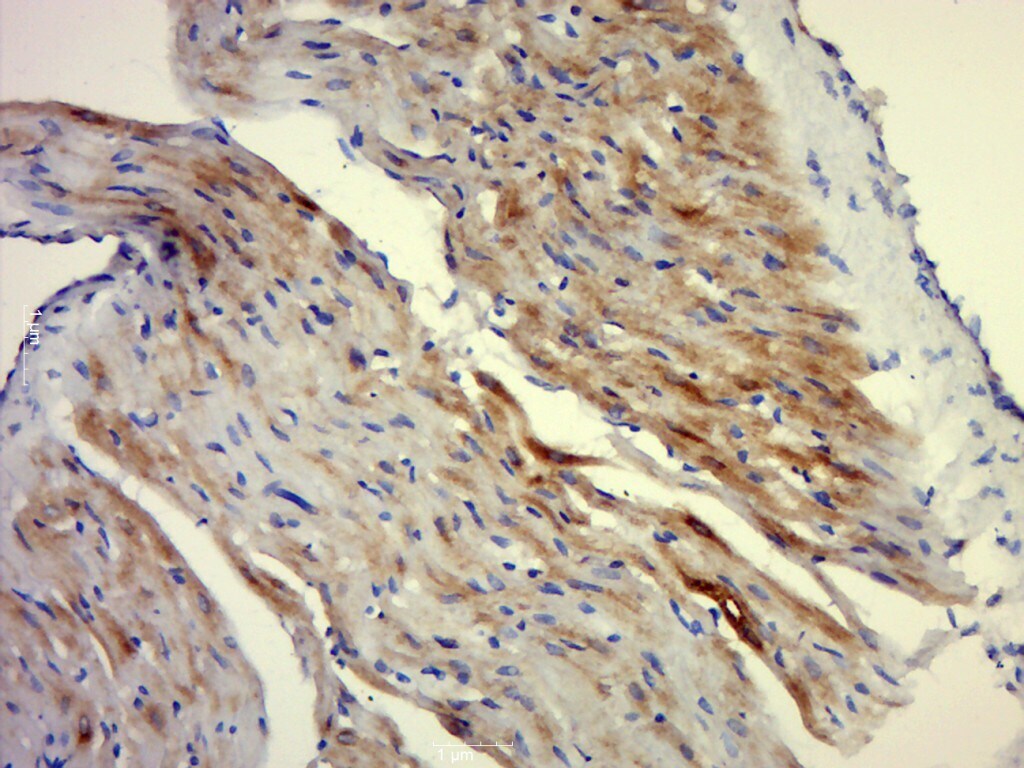

Supportive validation

- Submitted by

- Invitrogen Antibodies (provider)

- Main image

- Experimental details

- Paraformaldehyde-fixed, paraffin embedded rat heart; Antigen retrieval by boiling in sodium citrate buffer (pH6.0) for 15min; Block endogenous peroxidase by 3% hydrogen peroxide for 20 minutes; Blocking buffer (normal goat serum) at 37°C for 30min; Antibody incubation with MRas Polyclonal Antibody, Unconjugated (bs-1882R) at 1:400 overnight at 4°C, followed by a conjugated secondary for 20 minutes and DAB staining.